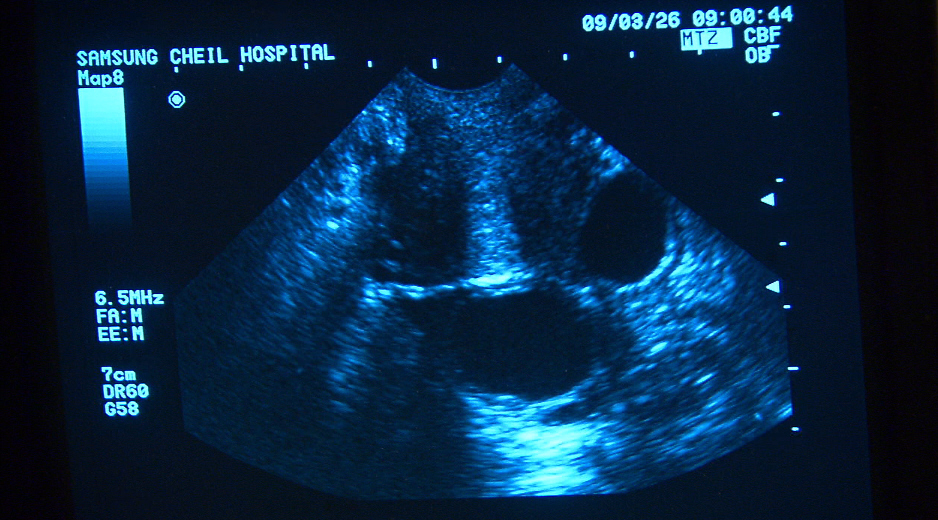

현재 지원자들의 호르몬 상태를 파악하기 위해 혈액 검사와 질 초음파 검사를 실시했다. 과연 이들의 결과는 어떠할까?

당뇨, 고혈압, 비만을 함께 가지고 있던 36세의 김수정(가명) 씨,

월경이 불규칙하고 임신이 잘 되지 않아 불임클리닉을 다니던 중 우연히,

자궁내막암이 발견되었다.